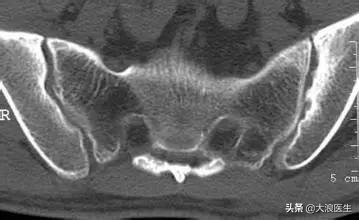

她听从了我的意见有空走走,走完确实症状比较缓解了,但是久坐会加重,早上起来也偶尔会酸胀。我虽然当时听起来觉得有点不对劲,但是理所当然地觉得这只是一个过程而已,便没有太多想法。再接着治疗几天后我越发觉得不对劲,也正好让他再去做个腰CT,这一次问题就浮现出来了,“双侧骶髂关节炎,强直性脊柱炎可能”。这时候我觉得问题可能就出来了,也就是为什么我之前的治疗反复的原因了。

双侧骶髂关节炎

她的腰椎CT是去年8月做的,到现在已经半年多了,之前的腰部CT只有少部分骶髂关节影像,也没有人考虑到。她已经走访好多个医院和医生,每次都是按照腰椎间盘突出治疗,每次也只是缓解一阵子。我也因为一开始想为患者省钱就没再让她再做影像学,患者也不愿意再承受射线,所以也忽视了,但是这一次感觉问题终于找出来了。现在把她转诊介绍到这方面专家治疗,服用药物剩余的症状基本已经缓解,现在早上起来也没有明显的腰骶部酸胀了。